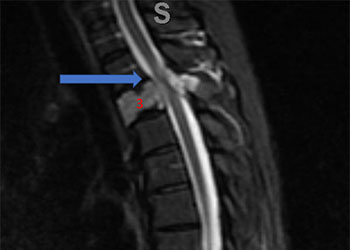

Spine:

Thoracic Spinal Cord Tumor Case Presentation

Author: Xavier P. J. Gaudin D.O., F.A.C.O.S., Read More!